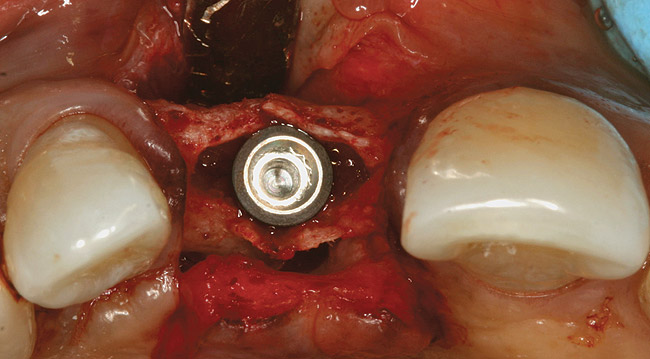

Tapered osteotomes were used to expand the ridge completely to the working length, which was at least 10 mm (Figure 5). It should be noted that if too much resistance is encountered, a drill smaller in diameter than a previously used osteotome can be used along the palatal wall. An implant was then placed into the osteotomy created by tapered osteotomes (Figure 6). Minor cracks were found in the middle of the expanded buccal plate during and after implant placement. Particulate bone allograft (freeze-dried bone allograft) was used to fill the gap between buccal and palatal alveolar plates, and another bone graft (bovine bone mineral) was packed outside the expanded buccal plate. A resorbable membrane was placed over the buccal plate and bone grafts (Figure 7 and Figure 8).

Figure 6  Implant placement. Note minor cracks at the middle of expanded buccal plate.

Figure 6